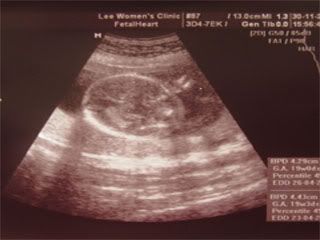

Went to see sinseh for my sprained ankle at work last 2 days. Recky for bridal studios for the whole day. Shucks. Ultrasound scans are scanned yesterday. Just photo updates today.

Her heartbeat.